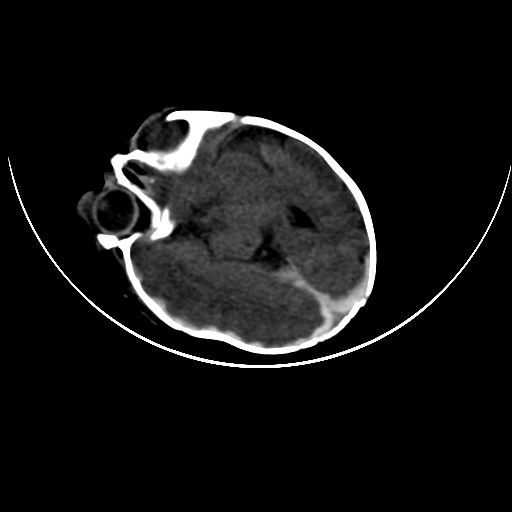

双侧硬膜下血肿并蛛网膜下腔出血。

双侧硬膜下血肿并蛛网膜下腔出血

硬膜下及蛛网膜下腔出血。

hie 蛛网膜下腔出血,硬膜下血肿。

hie;双侧硬膜下血肿并蛛网膜下腔出血

hie,双侧硬膜下血肿并蛛网膜下腔出血

双侧硬膜下血肿并蛛网膜下腔出血,考虑维生素k缺乏引起.

较大范围出血,应考虑维生素k缺乏引起,结合临床吧。

好像脑实质没有明显低密度影,各位大侠怎么支持hie呢?